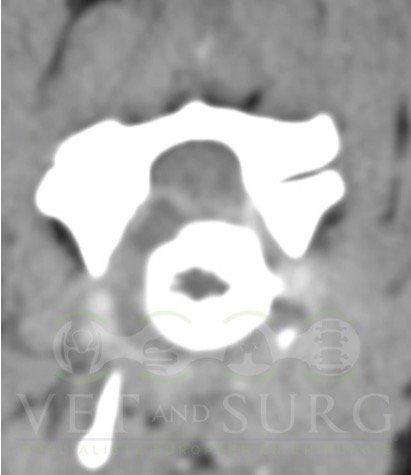

Hernie discale chez un bouledogue de 5 ans

Georges est présenté pour une paralysie des deux membres postérieurs.

Le scanner du rachis révèle une hernie discale en L3-L4 comprimant sévèrement la moelle épinière.

Une hémilaminectomie a été réalisée et le matériel hernié a été retiré pour décomprimer la moelle épinière.